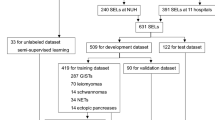

Thirty sets each of EUS images with SELs ≥ 20 mm or < 20 mm were prepared for diagnosis by an EUS diagnostic system with AI (EUS-AI) and three EUS experts. The EUS-AI and EUS experts diagnosed the SELs using solely the EUS images. The concordance rates of the EUS-AI and EUS experts’ diagnoses were compared with the pathological findings of the SELs.

The accuracy, sensitivity, and specificity for SELs < 20 mm were 86.3, 86.3, and 62.5%, respectively for the EUS-AI, and 73.3, 68.2, and 87.5%, respectively, for the EUS experts. In contrast, accuracy, sensitivity, and specificity for SELs ≥ 20 mm were 90.0, 91.7, and 83.3%, respectively, for the EUS-AI, and 53.3, 50.0, and 83.3%, respectively, for the EUS experts. The area under the curve for the diagnostic yield of the EUS-AI for SELs ≥ 20 mm (0.965) was significantly higher than that (0.684) of the EUS experts (P = 0.007).